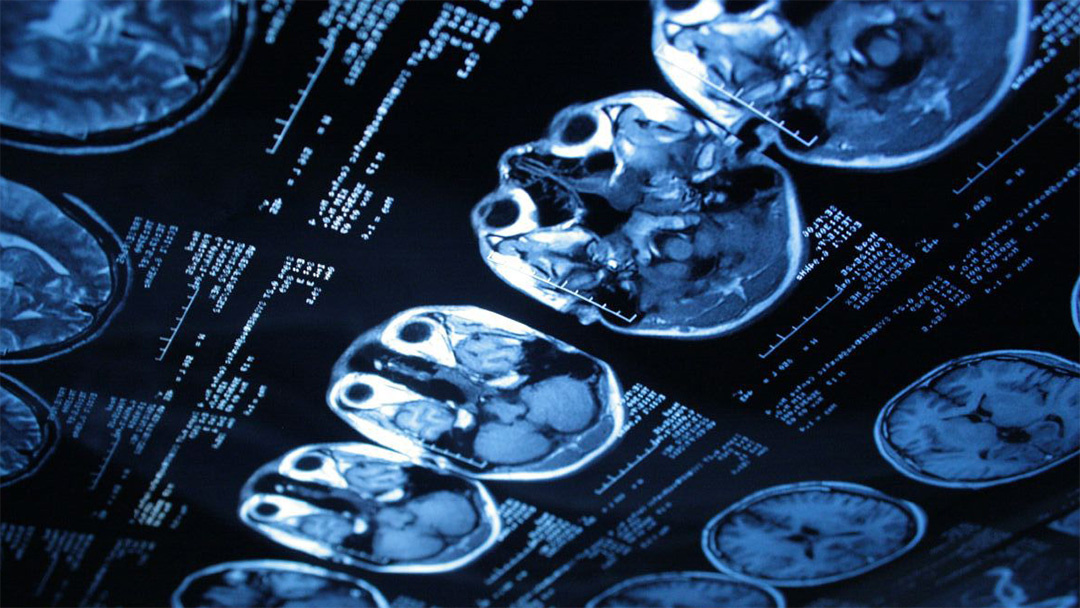

В России создан математический алгоритм, значительно улучшающий изображения, полученные при компьютерной томографии. Института прикладной математики Дальневосточного отделения Российской академии наук разработали новый алгоритм для компьютерной томографии. Он использует экстраполяцию данных многократного импульсного зондирования и опирается на обратное преобразование Радона. Алгоритм предполагает два сканирования одного объекта с минимальными различиями в настройках. При сопоставлении этих слегка размытых наборов данных математическая экстраполяция позволяет реконструировать сверхчёткое изображение. По своей сути это похоже на пару аналогичных и недостаточно чётких фотоснимков, при сопоставлении которых получается третье изображение с достаточной резкостью. И при этом применяется математическая экстраполяция. Эффективность метода была проверена на классической тестовой модели — фантоме, имитирующем срез головного мозга. В случае, если два близких элемента сливались в одно пятно, алго

Эффективность метода была проверена на классической тестовой модели — фантоме, имитирующем срез головного мозга. В случае, если два близких элемента сливались в одно пятно, алгоритм успешно разделял структуру. Компромиссом выступает небольшая доза облучения при втором сканировании, однако при этом возрастают точность и детализация.